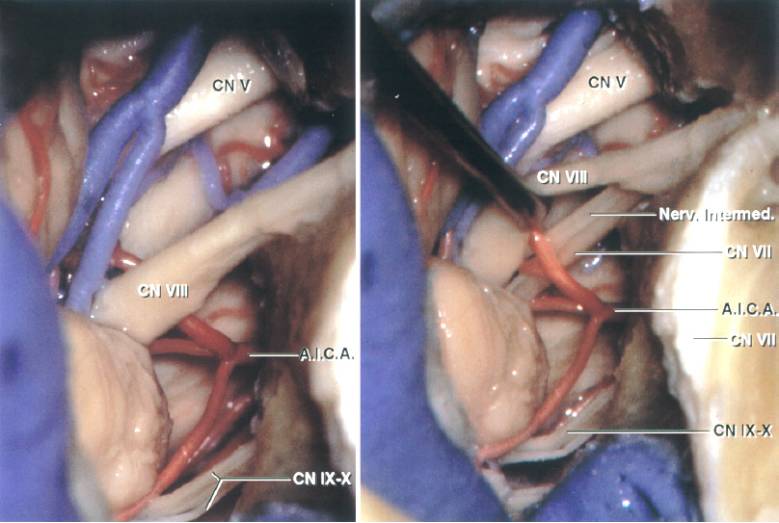

图2. TL入路所显露的CP角解剖:颈静脉球阻碍了对后组颅神经进入颈静脉孔部位的观察;移位前庭蜗神经以暴露前方的面神经。(图片由AL Rhoton,Jr授权)